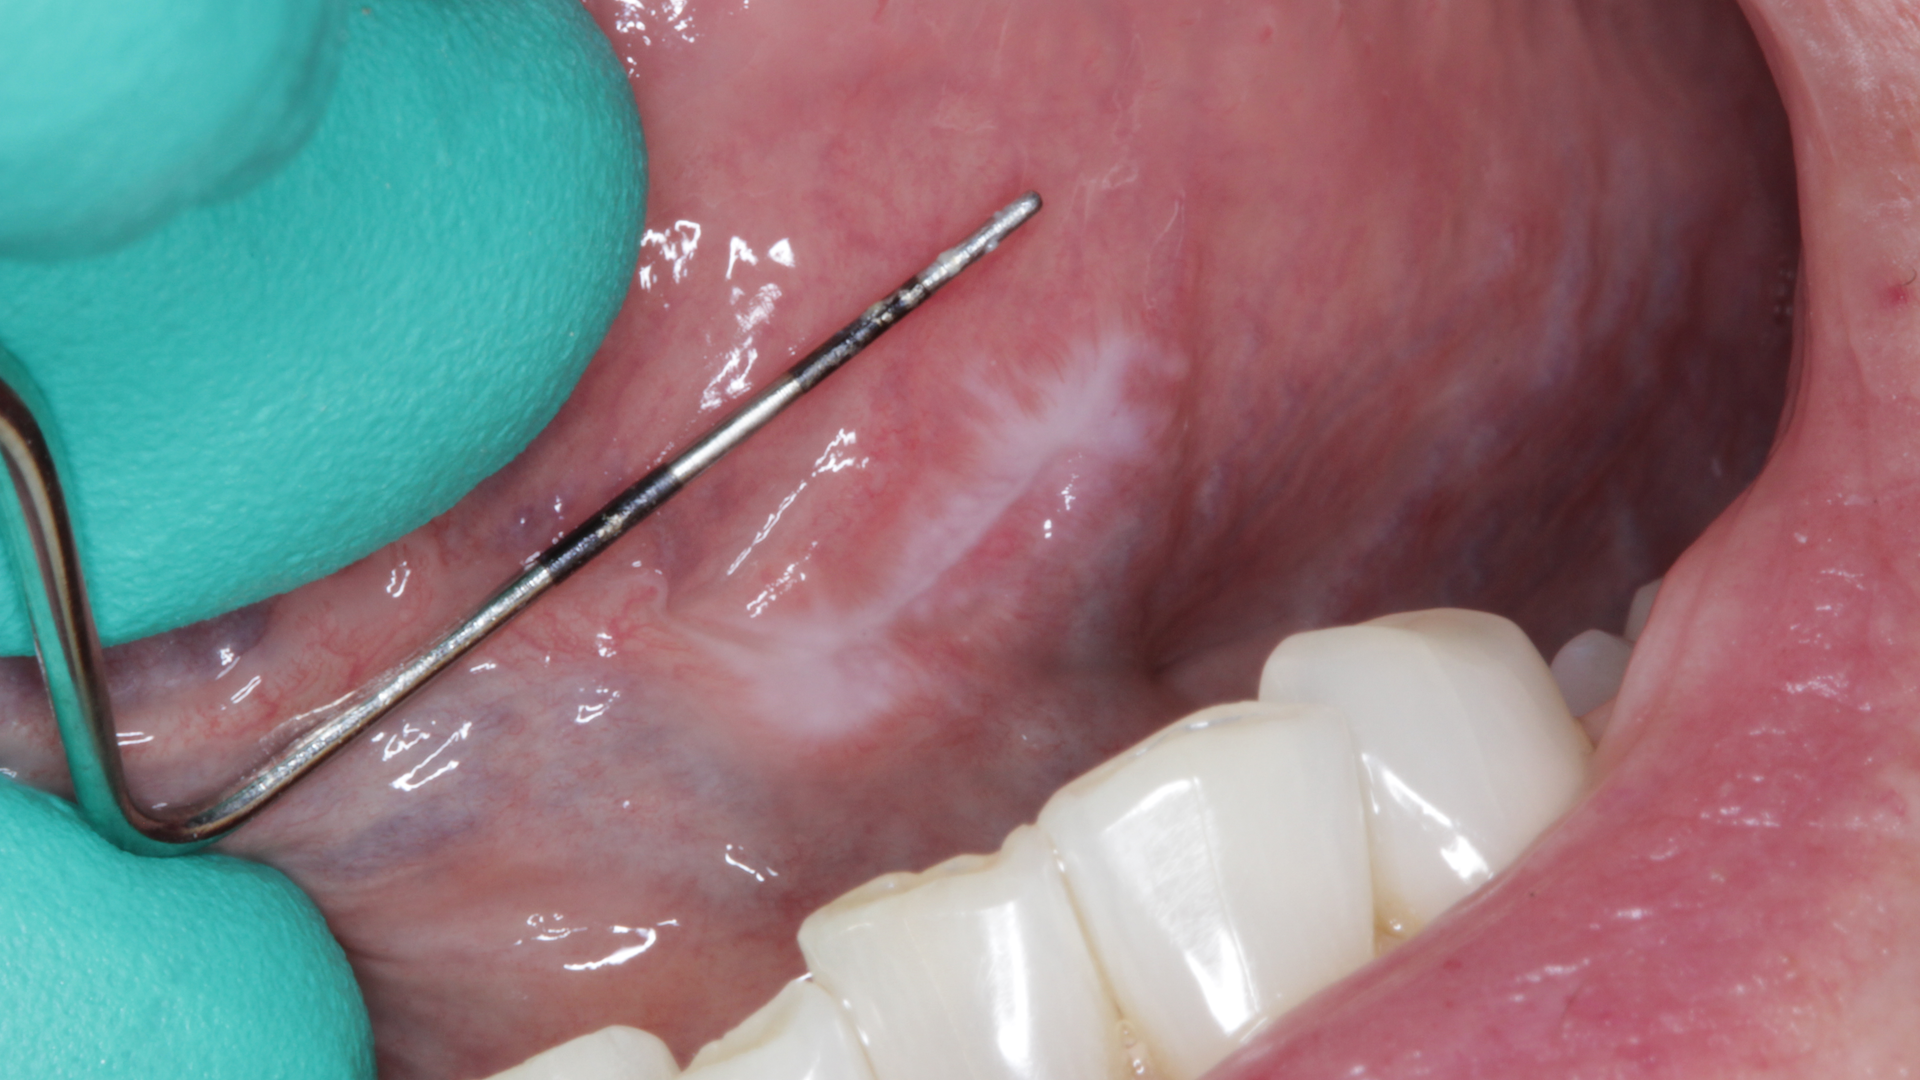

During her routine oral screening and exam, a 9 mm x 3 mm white leukoplakic patch of tissue on the left ventral surface of the tongue was noted. It was not tender to palpation, could not be scraped off, and the patient was unaware of its presence. It was recommended that the patient come back in two to three weeks to assess for continued presence.

The patient was referred to an oral surgeon where evaluation and an excisional biopsy were performed.

Definitive diagnosis: Keratosis with lichenoid chronic inflammation

In this particular case, the patient was a nonsmoker, and the etiology of the lesion was unknown; this alone put her in a high-risk category.

The diagnosis of lichenoid chronic inflammation is a form of “epithelial dysplasia with an associated dense infiltrate of lymphocytes that bears a striking resemblance to the dermatologic/mucosal condition of lichen planus; when an epithelial dysplasia has multiple histologic features in common with lichen planus, it is termed lichenoid dysplasia.”2 Treatment for these types of lesions is palliative unless they become widespread, persistent, or uncomfortable, in which case the use of topical steroids is common and effective.

Since the lesion in said patient was benign and excised completely, no further follow-up was recommended.